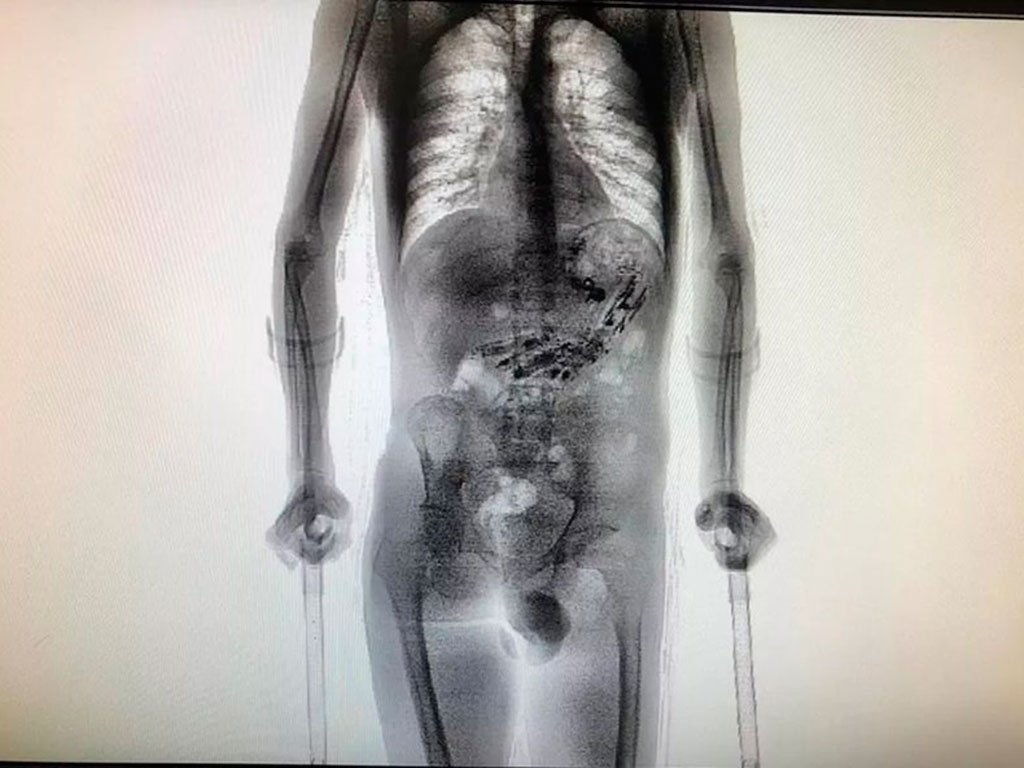

[caption id="attachment_64194" align="alignnone" width="768"] Ao passar por um scanner de revista corporal, foram encontrados nove celulares e mais 52 objetos como cabo USB, isqueiro, drogas, entre outros. Divulgação[/caption]

Ao passar por um scanner de revista corporal, foram encontrados nove celulares e mais 52 objetos como cabo USB, isqueiro, drogas, entre

outros.

Os agentes levaram o preso até o Complexo Penitenciário do Estado, em São Pedro de Alcântara, onde realizaram nova inspeção de imagens com

o aparelho de scanner e detectaram os objetos metálicos no estômago.